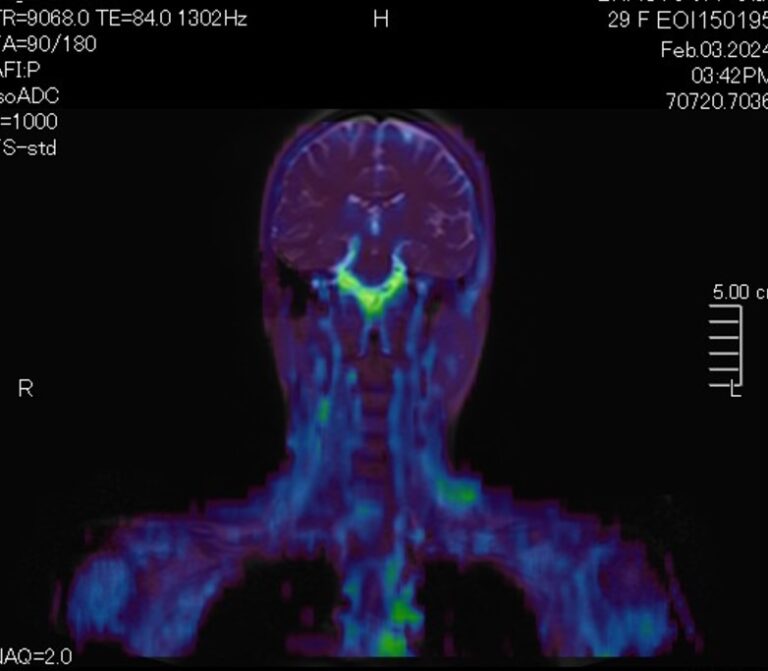

Скрининговое обследование всего тела с помощью метода магнитно-резонансной томографии включает в себя сканирование головы, шеи и туловища с органами брюшной полости, забрюшинного пространства и малого таза.

В нашей клинике МР-скрининг всего тела проводится на новейшем высокопольном томографе экспертного класса TOSHIBA VANTAGE TITAN 1,5 Тесла. Аппарат послойно сканирует структуры всего тела в различных плоскостях в виде тончайших срезов с шагом от 1 мм, затем посредством инновационных компьютерных программ преобразует полученные данные в трехмерные изображения превосходного качества.

Метод позволяет выявить бессимптомные потенциально опасные для жизни состояния, например опухолевые образования, которые долгое время себя никак не проявляют и могут обнаруживаться уже в запущенных случаях. К примеру, опухоли яичников, почек, печени, когда раннее выявление процесса значительно повышает шансы пациента на успешное лечение и выздоровление. Также МР-скрининг может проводится в профилактических целях пациентам, у которых есть близкие родственники с онкопатологией, чтобы вовремя выявить начало болезни.